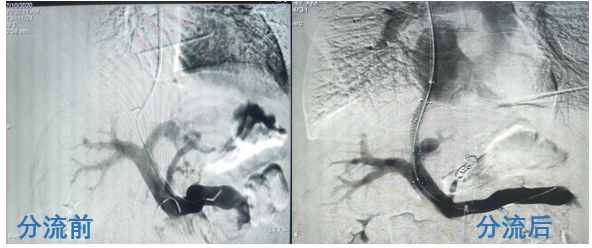

2020年7月,我院导管介入室主任王华带领介入团队先后自主完成了两例经颈静脉肝内门体静脉分流术(简称TIPS手术)。近日,两名患者恢复良好顺利出院,标志着我院的介入手术水平又上了一个新台阶。

接受该手术的两名患者均来自外地,因“呕血、黑便”辗转于多家医院,诊断“肝硬化、门静脉高压、食管胃底静脉曲张”后治疗效果不佳,慕名来到我院寻求帮助。在对患者进行详细的体格检查后,王华主任立即组织全体科室成员研究讨论,评估患者病情,制定手术方案。由于患者肝硬化严重,不能耐受传统开腹手术,最终决定采用目前国内先进的TIPS肝脏介入手术,通过降低患者门脉压,从根本上达到治疗的目的,最大程度降低再出血的风险。主管医生与家属交流、沟通后得到了患者及家属的理解和同意。于是,王华主任带领导管介入团队团结一致、攻坚克难,先后为两位患者实施了TIPS手术,手术历时4个小时,最终顺利完成。患者术后观察未再出血,门静脉压力降至正常,恢复良好。

我国是肝硬化大国,呕血、黑便或腹水是肝硬化失代偿期导致门静脉高压最常见的并发症。药物、内镜下套扎或硬化治疗只是姑息性降低门静脉压力的方法,最早以前,外科分流手术能有效降低门静脉压力,但由于高死亡率、高并发症而逐渐被取代。目前,最有效的降低门静脉压力的方法就是TIPS手术,它通过在肝静脉与门静脉之间的肝实质内建立分流通道,以达到降低门静脉阻力、治疗消化道出血的目的。该手术技术难度大、风险高,因此能做TIPS手术的医生很少,至今很多地级市乃至省份TIPS手术仍是空白。